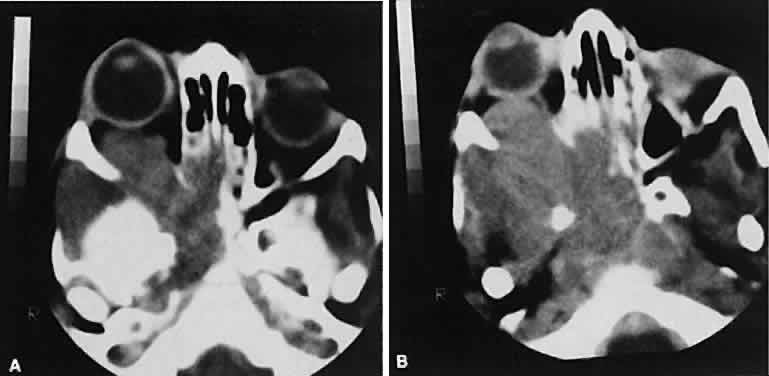

| Metastatic disease accounts for 2% to 10% of all orbital tumors.69,70 As a generalization, childhood metastases are from undifferentiated sarcomas, whereas

adult metastases are from postembryonal carcinomas. Radiographic evaluation can show either infiltrative or circumscribed masses. Some tumors display a predilection for metastasizing to certain structures, such as prostate carcinoma to bone and cutaneous melanoma to EOMs (Fig. 21). Evidence of bilateral disease at presentation ranges from 7% to 9%, with the prime example being neuroblastoma.71 |